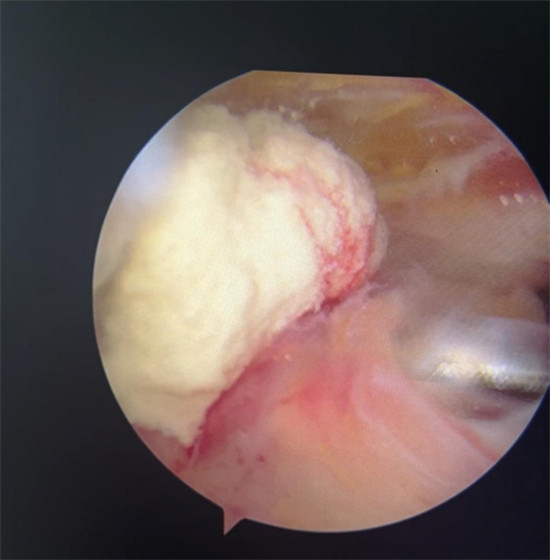

賀大媽慕名來廣安醫(yī)院找羅軍主任就診,面對羅醫(yī)生,賀大媽哭訴:“羅醫(yī)生,我真想剁下自己的這只胳膊。”羅軍主任根據(jù)患者的癥狀拍片,診斷為岡上肌鈣化性肌腱炎,隨后,羅醫(yī)生為李大媽進(jìn)行了肩關(guān)節(jié)鏡微創(chuàng)手術(shù),竟從她的右肩“擠”出“牙膏”。

鈣化性肌腱炎是一種自限性疾病,就是疾病發(fā)生發(fā)展到一定程度后,經(jīng)長期機(jī)體調(diào)節(jié)能夠控制病情發(fā)展并逐漸恢復(fù)痊愈。它分為四個(gè)階段:鈣化前期、鈣化形成期、鈣化吸收期、鈣化后期,往往在“鈣鹽斑塊”吸收時(shí),疼痛最劇烈,賀大媽就正處于“吸收期”。

是不是只要病人撐得住,讓鈣鹽吸收就沒事了?羅軍主任表示,經(jīng)保守治療無法緩解或病程長的患者,應(yīng)盡早采取手術(shù)治療。而且,部分患者鈣鹽無法完全吸收,拖下去只會使病情惡化,造成肩膀肩袖肌腱的損傷。